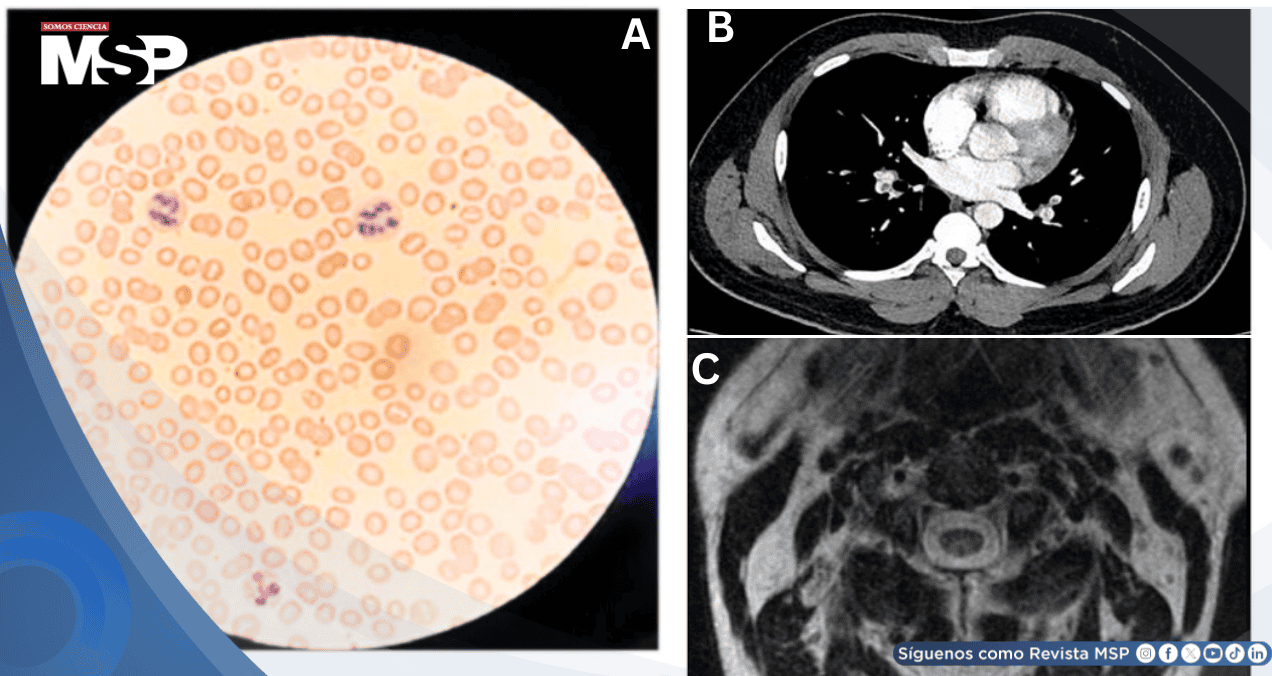

Los marcadores bioquímicos confirmaron la sospecha diagnóstica: nivel de vitamina B12 de 187 pg/mL (por debajo del rango normal), homocisteína marcadamente elevada en 67.9 micromol/L (más de cuatro veces el límite superior normal) y ácido metilmalónico de 2,417 micromol/L. La angiografía por tomografía computarizada del tórax reveló embolia pulmonar bilateral extensa comprometiendo múltiples arterias pulmonares segmentarias.

La resonancia magnética de columna torácica mostró áreas sugestivas de alteración en la señal medular, aunque los hallazgos fueron sutiles y posiblemente artefactuales.

El estudio dúplex venoso de extremidades inferiores documentó trombosis venosa profunda bilateral que afectaba las venas poplíteas izquierda y derecha, extendiéndose hacia la vena femoral superficial distal derecha. La angiografía por tomografía computarizada evidenció embolia pulmonar central bilateral con aplanamiento del tabique interventricular derecho, indicando sobrecarga ventricular derecha.

La resonancia magnética de columna cervical, torácica y lumbar mostró señal anormal en las columnas posteriores del cordón cervical y alteración de señal ubicada centralmente en el cordón torácico, hallazgos compatibles con degeneración combinada subaguda de la médula espinal.